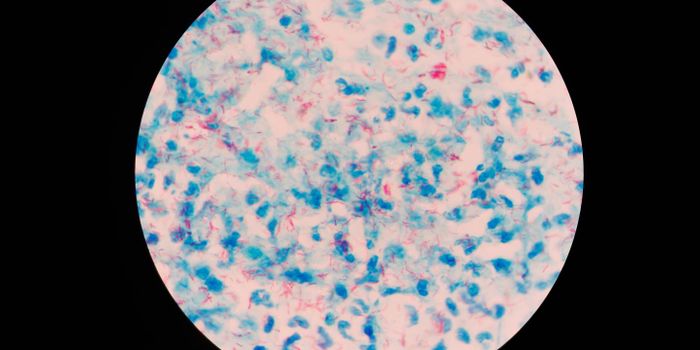

DEC 23, 2019Cell & Molecular BiologyIn 2018, around ten million people around the globe were sickened by tuberculosis (TB) and about 1.5 million people were ...

SEP 14, 2019Cell & Molecular BiologyTuberculosis (TB) is among the world’s leading causes of death, and is the primary cause of death in people who ar ...